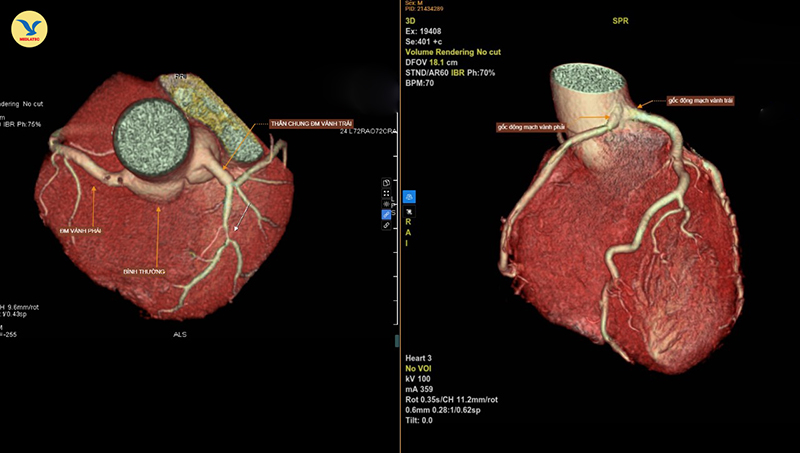

Hình ảnh chụp CTA 3D. Bên trái là động mạch vành bình thường. Bên phải là hình ảnh hai nhánh động mạch vành trái và phải xuất phát chung từ một gốc

Đây là một dị tật bẩm sinh hiếm, chỉ gặp dưới 0,05% dân số. Trong đó, type LII-B (phân loại Lipton) là biến thể có đường đi nguy cơ cao, khi động mạch vành phải xuất phát từ xoang Valsalva trái và chạy giữa động mạch chủ - thân động mạch phổi, dễ gây thiếu máu cơ tim và đột tử, đặc biệt khi gắng sức.